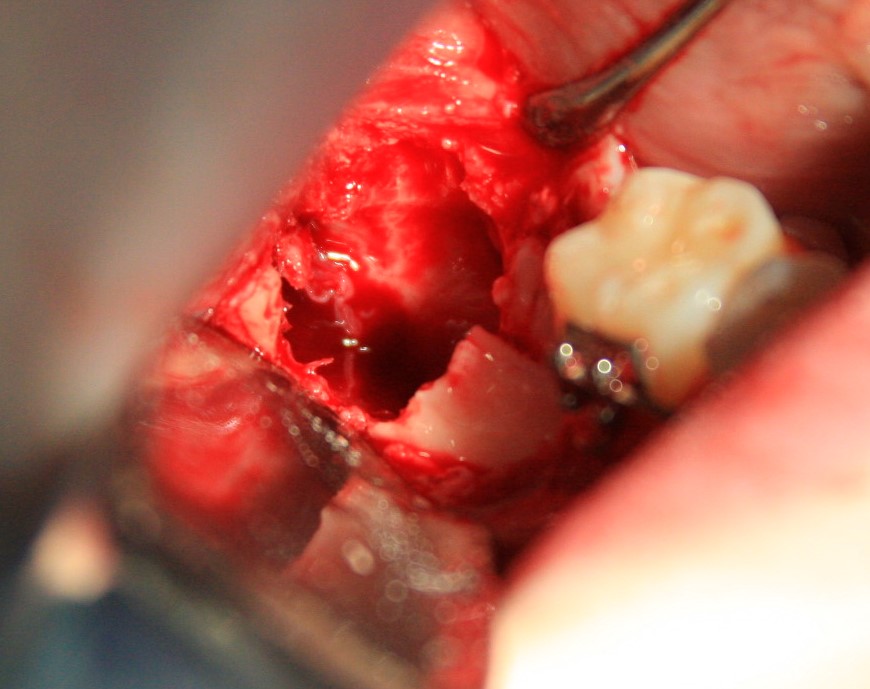

Далее, разрез. Создаем доступ к зубу. Для этого используется повышающий наконечник с соответствующими фрезами. Вот они, восьмерка и семерка:

Чтобы аккуратно удалить восьмерку и не повредить соседний зуб, мы делим ее на две части. НИКАКИХ МОЛОТКОВ И ДОЛОТОВ))) Все делается, исключительно, с помощью фрез:

После чего аккуратно удаляем коронку:

А через минуту — и корни зуба. Поверьте, это очень просто, для этого не нужно прилагать каких-то усилий. Достаточно просто включить голову.